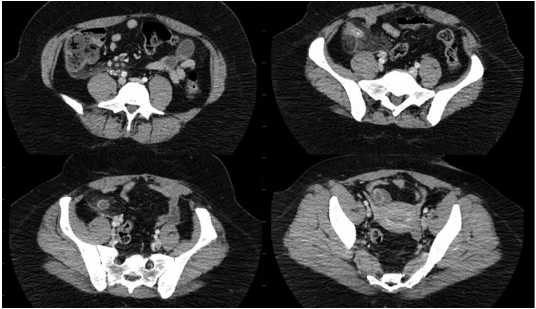

Mulher, 70 anos, DM tipo 2 e HAS, ambas com controle adequado. Hematoquezia há 3 meses. Refere emagrecimento não intencional de 10 kg, em 6 meses. Exames laboratoriais: Hb 10,9 g/dL, plaquetas 220 mil/uL,

Cr 0,95mg/dL, INR 1,0, R 0,95, PCR 15,2 mg/dL, ferritina 40 ng/mL, saturação de transferrina 12%, albumina

3,5 g/dL. Exames de estadiamento negativo para metástases. Realizados os exames diagnósticos a seguir.

(Arquivo pessoal; imagens usadas com autorização)

Qual é o diagnóstico e como deve ser feita a condução dessa paciente no pré-operatório?